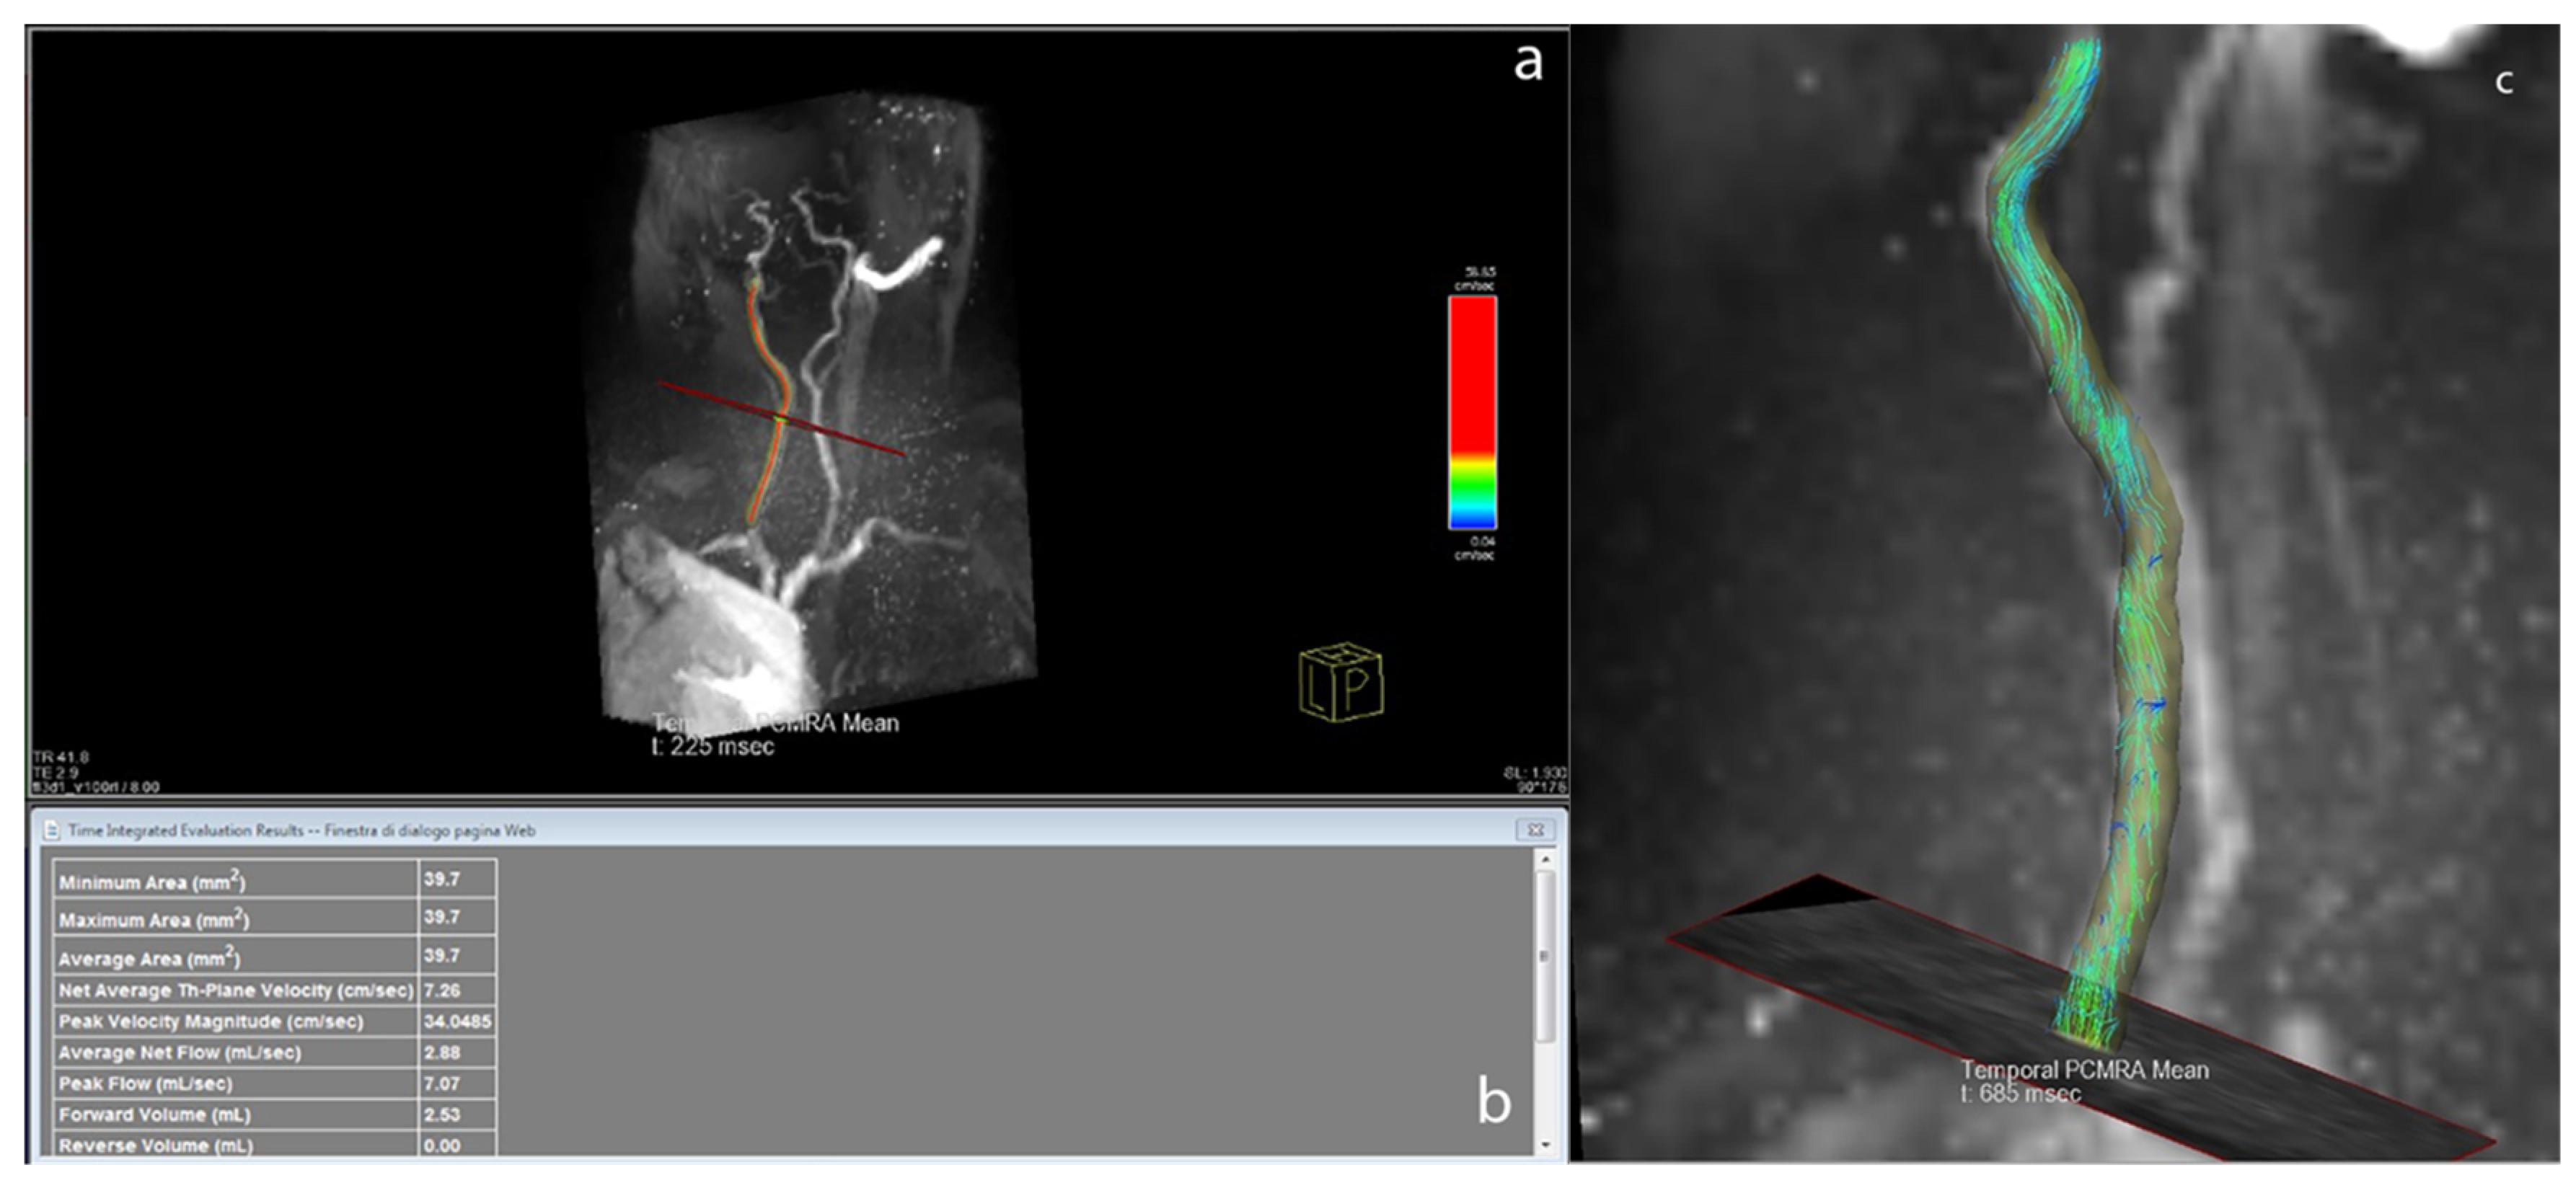

The 4D-flow data were processed with the prototype software 4D Flow Demonstrator v2.4 (Siemens Healthineers, Erlangen, Germany). In a first step, the entire slab was loaded, and background phase correction and antialiasing were applied. Then the user selected the vessel of interest on the magnitude images, where a centreline was automatically calculated. The region of interest included the visible portions of the common carotid artery (CCA) and the origin of the ICA and ECA after the bifurcation. Then, the user placed a plane orthogonal to the vessel centreline to retrieve flow characteristics. Figure 2 illustrates the flow plane positioning and the flow streamlines in the 4D-flow acquisitions. Three planes were selected with the aim of reproducing the same positions of the 2D-PC slices acquired in the CCA, ICA, and ECA.

Figure 2. Reconstruction of a carotid artery using 4D-flow software; (a) plane of interest is highlighted; (b) table with flow data from the plane shown in a; and (c) single frame from streamlines of common carotid artery and internal carotid artery.